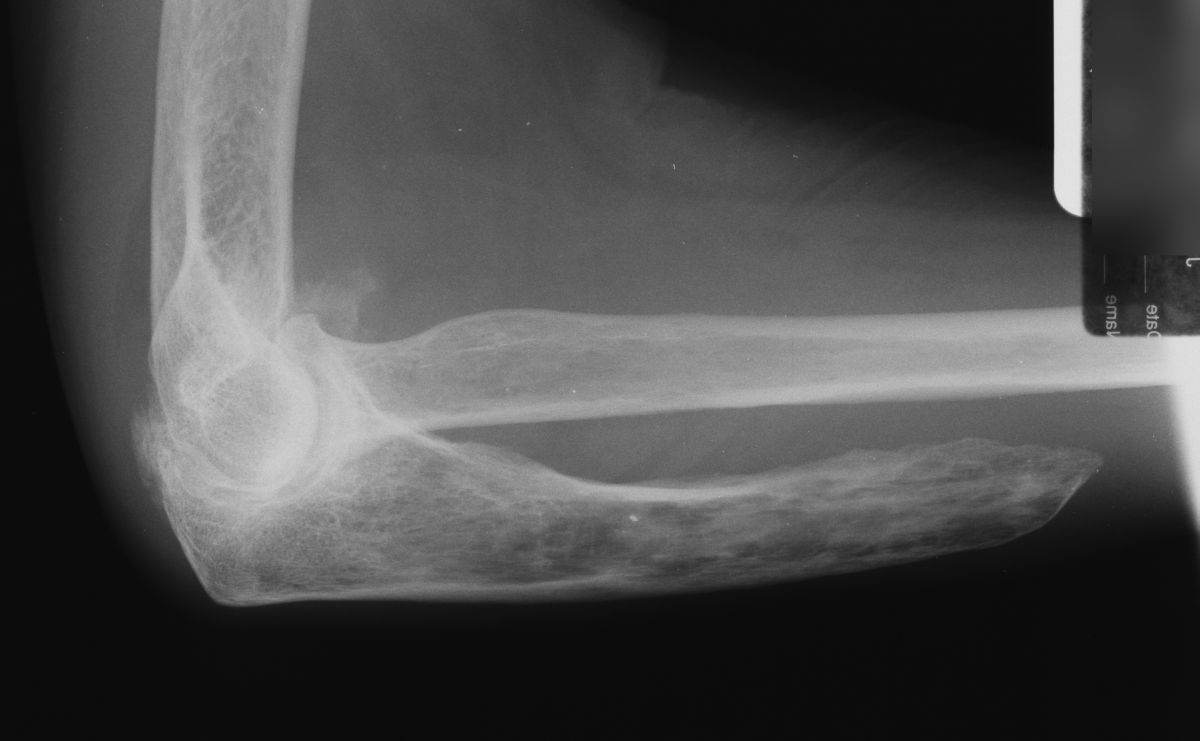

| Case 2. This 74 year old man presented with elbow pain years after wide excision of the central ulna and forearm radiation for a malignant tumor. The abnormal load on the radiocapitellar joint has resulted in degenerative changes. |